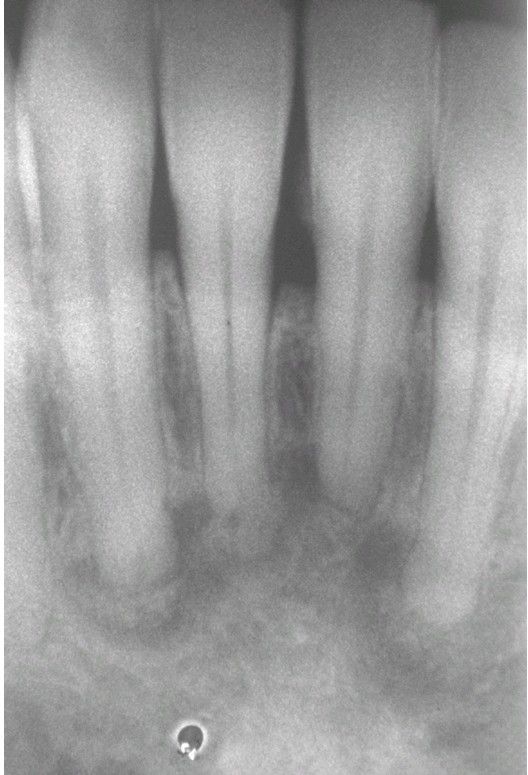

Periapical Cemento-Osseous Dysplasia.

Laterstage lesions exhibiting significant mineralization.